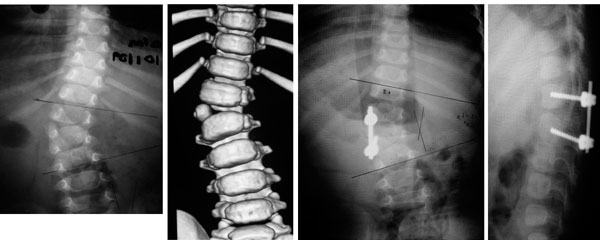

Paciente de 1 año y 8 meses con escoliosis congénita progresiva, se realizo resección de hemivertebra con colocación de tornillos transpediculares.